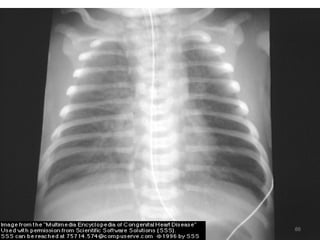

- CXR - Cardiomegaly

- Plethoric lung

CXR - Narrow base & uplifted apex

- A boot or wooden shoe

- decreased pulm. vascularity

- Right side aortic arch in 20%